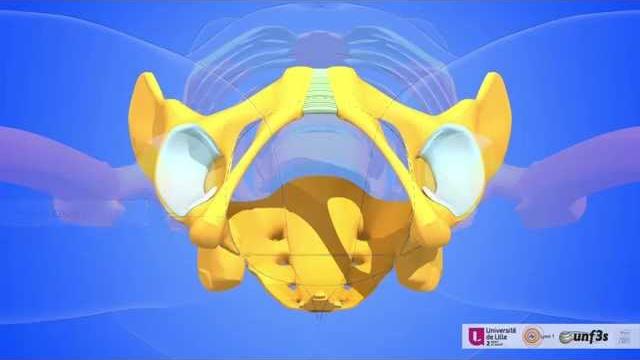

Girl pelvic

Для вашего запроса найдены видео: Guided meditation for pelvic floor relaxation | femfusion fitness, Best exercises for prolapse and bladder leaks safely strengthen your pelvic floor!, Clinical pelvimetry